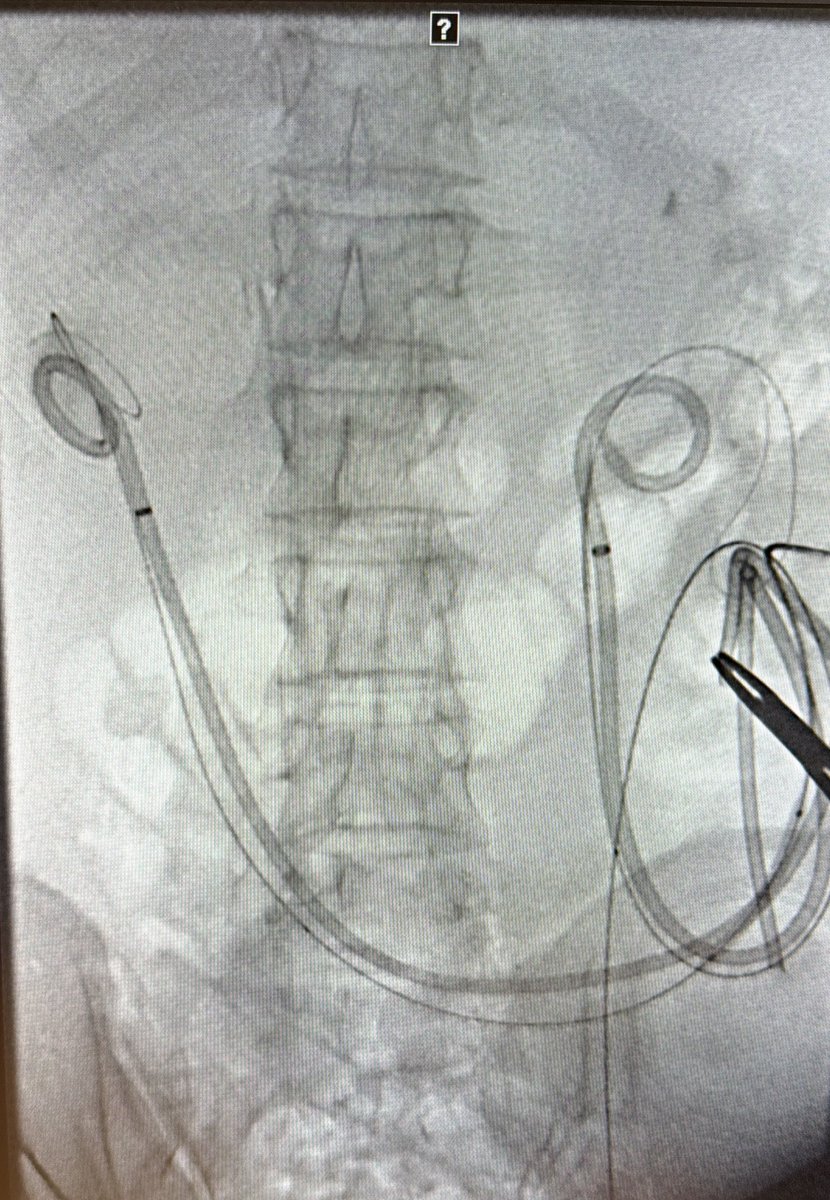

#CTO of Nephroureteral stents! Can’t cross with any wire on shelf! What’s your rec to help out your junior colleague to swap them ? May be your trick can come handy & help @SIRRFS one day ! @kmadass I know it ain’t arterial 😁 @keithppereira @SDhandMD @IRKhalsa @IR_Doctor

@t_intheleadcoat @SIRRFS @kmadass @keithppereira @SDhandMD @IRKhalsa @IR_Doctor Encrusted? These can go sideways fast if not careful. Often a glidewire can track alongside the stent (similar to clogged antegrade PCN/GJ tubes). 👀 to see what you did

@t_intheleadcoat @SIRRFS @kmadass @keithppereira @SDhandMD @IRKhalsa @IR_Doctor These are tough cases for a routine exchange- and go by many names- reverse PCN- diversionary catheter- and "single J"- if no wire will go through, can always take a KMP alongside it, get a wire up and slowly pull as to not dislodge your buddy wire, otherwise, crossing catheter